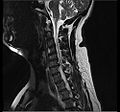

Cervical disc herniation

Herniated disc at C6–C7 level

Cervical disc herniations occur in the neck, most often between the fifth and sixth (C5–6) and the sixth and seventh (C6–7) cervical vertebral bodies. There is an increased susceptibility amongst older (60+) patients to herniations higher in the neck, especially at C3–4.[21] Symptoms of cervical herniations may be felt in the back of the skull, the neck, shoulder girdle, scapula, arm, and hand.[22] The nerves of the cervical plexus and brachial plexus can be affected.[23]